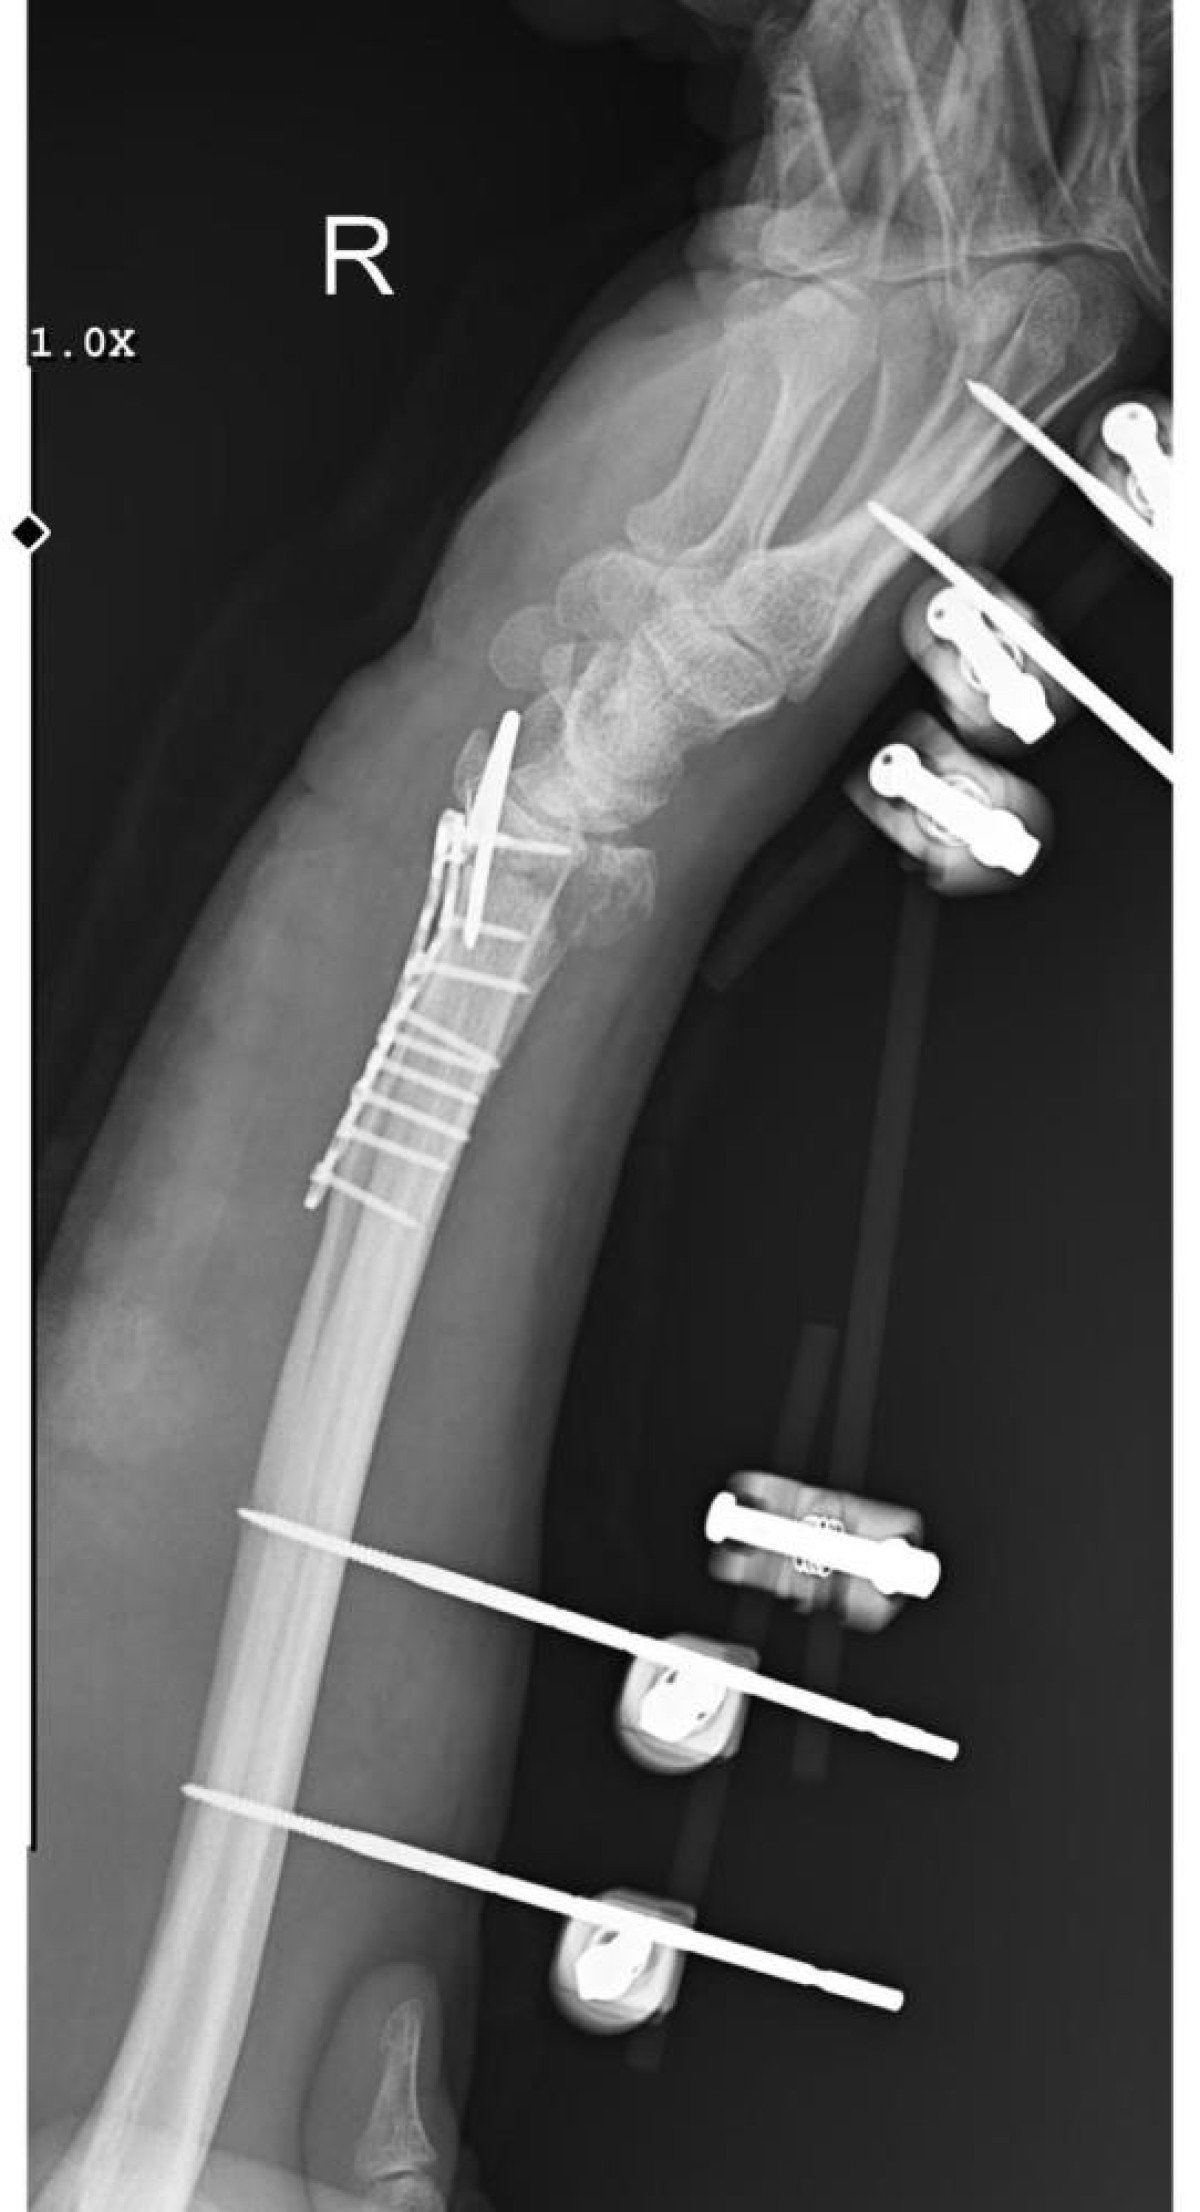

11 PLATİN TAKILDI, KALICI HASAR OLUŞTU

Tedavi süreciyle ilgili konuşan Arslantaş, bilek kemiğine 11 adet platin yerleştirildiğini ve uzun süre kolunu kullanamayacağını belirterek, “Yaklaşık 3 saat süren bir ameliyat geçirdim. Bileğimde 15 dikiş ve 11 platin var. Doktorlar, kalıcı his ve hareket kaybı olabileceğini söyledi. Önümde uzun ve zorlu bir tedavi süreci var” dedi.